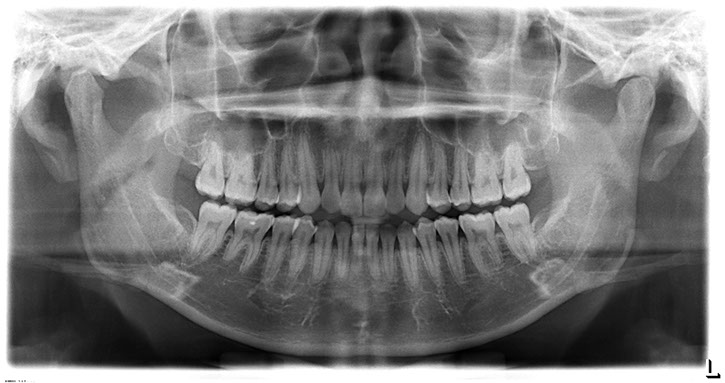

全口掃描X光攝影 (Panoramic x-ray)

全口掃描X光攝影(Panoramic x-ray)是一張環形掃描之全景X光攝影,它是齒顎矯正及植牙手術前一張不可或缺的影像,可以觀看到我們上下牙齒的形態、排列狀況,以及牙齦齒槽骨高度、與下頷神經管相關位置,亦可縱觀到顳顎關節(TMJ)、鼻竇(Sinus)、埋伏齒、囊腫(Cyst)或腫瘤(Mass)...等等,同時可約略評估骨質狀態,因此它也常是醫療型全身健康檢查的例行項目之一。

一張好的全口掃描X光除了必須要有專業放射師的擺位、機器準確的定位外,影像清晰度的高低決定了它的診斷價值,我們提供高解析的數位化影像,亦可輸出雷射傳統X光片,讓您的牙醫師取得所需形式的報告來為您做最好的診斷。